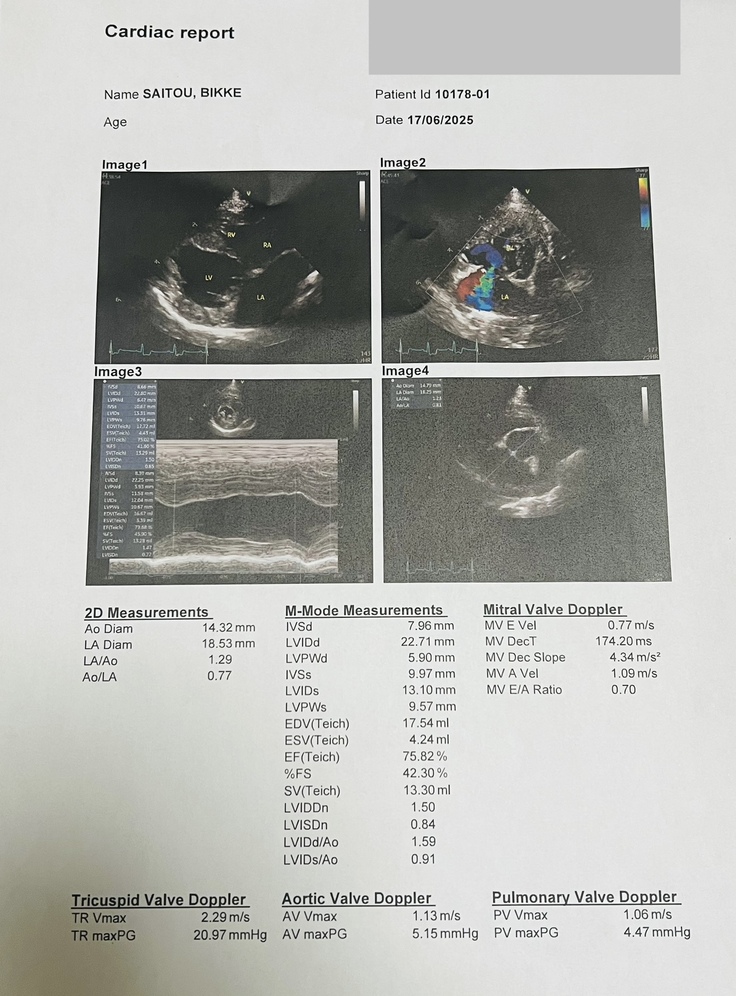

6月17日(火)、ビッケは三ヶ月検診を受けました。

診察の結果、経過は順調で、血栓の予防薬も心臓の薬もすべてやめることができました。

一部逆流は認められましたが、心臓肥大もなく経過観察となりました。

先生からは「6ヶ月から9ヶ月の間に再発する場合もあるので、何かあればすぐに連絡してください」とのお話があり、次回は12ヶ月検診です。